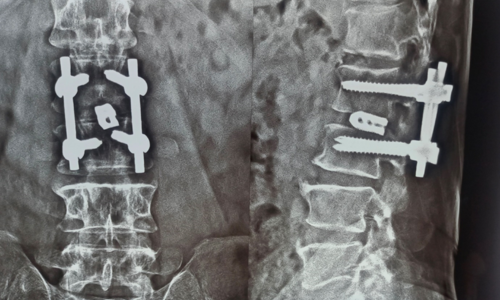

Posted on Nilesh KaduTrustindex verifies that the original source of the review is Google. I visited Dr. Nitish Agarwal for my severe back pain and shoulder issue. He checked my MRI very carefully and gave the perfect diagnosis. Yesterday, he performed the procedure (Root Block and Shoulder Injection), and it was completely painless. He is an expert and targeted the exact nerve point causing the trouble. Very helpful and humble doctor. Highly recommended for anyone with spine problems.Posted on Raju GorkhaTrustindex verifies that the original source of the review is Google. I was unable to make movement and suffered from right foot drop which is equal to halfway paralysis. Dr. Nitish Agarwal performed very fine microscopic surgery on L3, L4 & L5. After 90 days under his treatment I could go for a walk min. 6 kms a day, I have started my regular activities after 120 days. Thank you so much Dr. Nitish Agarwal sir.Posted on Pururaj GuravTrustindex verifies that the original source of the review is Google. I was suffering from severe back pain, and Dr. Nitish Agrawal has been extremely supportive throughout my treatment. He listened carefully, explained everything clearly, and guided me very well. His treatment has really helped me recover. He is one of the best spine specialists — highly recommended!Posted on Vinal AgrawalTrustindex verifies that the original source of the review is Google. I had consulted many doctors before Dr Nitish for my mother's spine issue,most recommended complex procedures and surgeries. Fortunately we found Dr Nitish and it has been life changing for my mother,she was in immense pain before the simple surgery he did. It's rare to find a surgeon who explains everything in detail and provides such exceptional care even after the surgery. I Would highly recommend him.Posted on Ajinkya MohadkarTrustindex verifies that the original source of the review is Google. My mother had sustained a fracture to her right hand wrist and we were worried about her recovery due to age factor. One of our family Doctor referred us to Dr. Nitish Agrawal and we visited Dr. Nitish Sir. Dr. Nitish sir ensured that my mother don't need a surgery and treated her by application of plaster (temporary and then cast-iron or Firm plaster) with certain orthopaedic treatment to hand and prescribed oral medication for ensuring recovery is faster without any surgery. Attaching the photo of xray which shows recovery of wrist bone which has rejoined and we are still continuing treatment to ensure my mother is fully recovered and is fit. Thank you Dr.Nitish Agrawal for your support.Posted on Samadhan LokhandeTrustindex verifies that the original source of the review is Google. Hi everyone, myself Samadhan. I was suffering from severe spine pain for a long time, and one of my friends suggested I visit Dr. Nitish Agarwal. Honestly, that was the best advice! Dr. Nitish listened to my problem very patiently, explained the cause in detail, and gave me the right treatment. I started feeling better within a short time. He is very polite, knowledgeable, and truly cares for his patients. I highly recommend Dr. Nitish Agarwal for anyone dealing with spine or back pain. Thank you, doctor, for your excellent treatment and support!Posted on POOJA JAGDALETrustindex verifies that the original source of the review is Google. Dr. Nitish Agrawal is an excellent spine specialist who patiently listens, explains the problem clearly, and provides the best treatment options.Posted on vipul pardeshiTrustindex verifies that the original source of the review is Google. Dr.Nitish sir is an incredible surgeon. I had excellent results from my recent spine surgery. The entire process, from consultation to recovery, was handled with professionalism and care. The outcome has been life-changing. I highly recommend Dr.Nitish agarwal to anyone in need of a spine surgeon.Posted on Deepak JadhavTrustindex verifies that the original source of the review is Google. A few months back I took treatment for my back pain from dr. Agarwal sir ...last 7-8 years i was suffering with low back pain,unbale to stand for more than 10 minutes..My low back hurts continuously, and also left leg pain was unbearable....i try every possible way of treatment from various suggestion...After several treatment...one of my relative suggested dr. Nitish Agarwal sirs name then I visited Dr. Nitish Agarwal sir in clinic. He suggested me x ray and MRI. On that basis he advise me caudal Block with root block with facet block for pain management. After block my pain goes with in a week. He advise me regular Physiotherapy at home. Now after regular exercise I am pain Free. Dr. Nitish Agarwal is a good doctor for any spine related problem.... Thank u dr. Agarwal Sir 🙏Posted on Kumar BTrustindex verifies that the original source of the review is Google. My wife had major infection in neck and lower back. She was bedridden. her legs and hands were weak. Then we admit her under Dr. Nitish Agarwal sir and did MRI. He explained that she is having major infection in cervical and lumbar spine. Due to infection her spinal cord is compressed so she was not able to walk. Then sir did operation for neck and removed infected tissue and spinal cord is freed and put a plate. Her lower back is treated with medicine only. She was given 2 months antibiotics by saline and 5 months oral antibiotics were given. He also advised regular exercise. After 15 days of surgery she started walking with support. Now after 1 year she is completely alright and walking like a normal person. She is regularly doing all her activities. Now she can also travel by 2 wheeler. Thank you to Dr. Nitish Agarwal sir for his expert work in spine. I recommend Dr. Nitish Agarwal for any spine related problem.